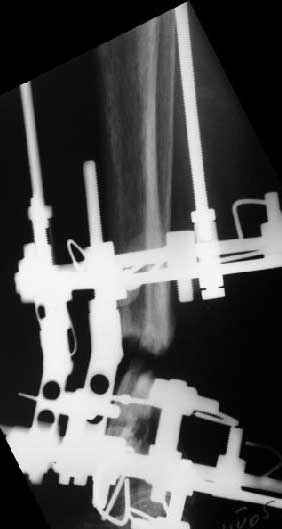

В общем, начали c аппарата - нложили, малоберцовую внизу пересекли, выбрали люфт, раз дальше сопротивление пошло - выведем постепенно.

Картинки приложены. Жду комментариев.

e> Какова была подвижность в зоне несращения после остеотомии малоберцовой

e> кости?

Примерно такова, как было на снимках в аппарате. Все, что относительно свободно было, выбрали, а дальше уже было тугое сопротивление тканей.

e> Была ли возможность одномоментной коррекции оси б.б кости и если да,

e> то почему не штифтование, а аппарат?

Аппарат - чтобы плавно исправить ось. В приложении - снимки на момент окончания коррекции в аппарате, фото с операции, и послеоперационная рентгенограмма.